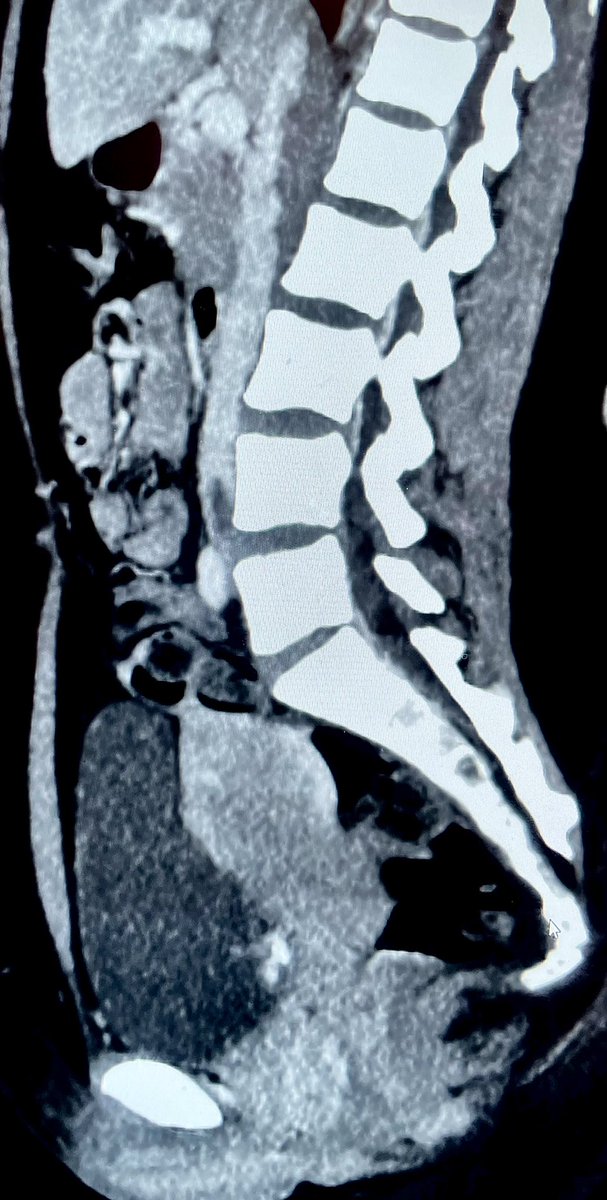

39 yo F on #OCPs. Acute Lt. LL pain n swelling, extensive #DVT, CT confirms #MayThurner #syndrome. Thrombolysis, Thrombectomy done using #AngioJet, followed by #venoplasty & stenting. #IRad is #OneStopShop! @SIRspecialists @pakIRSP @cirsesociety @rahilkassamali @drsaadrehman 1/2